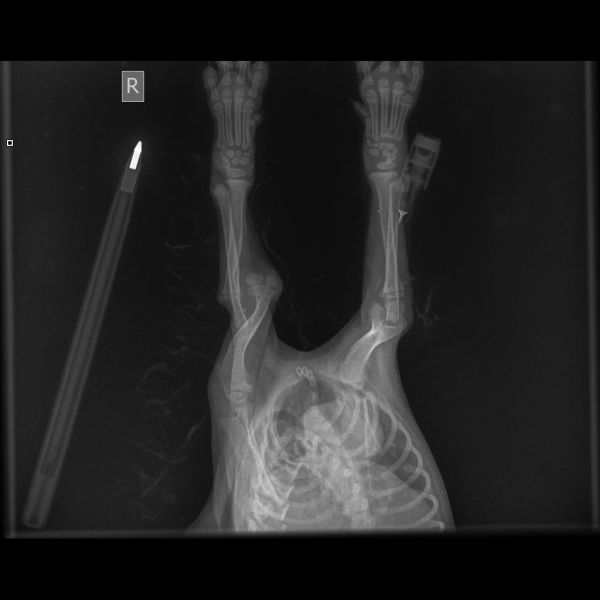

Give the gift of better health and wellbeing. An x-ray can help identify the best way to treat an animal in need.